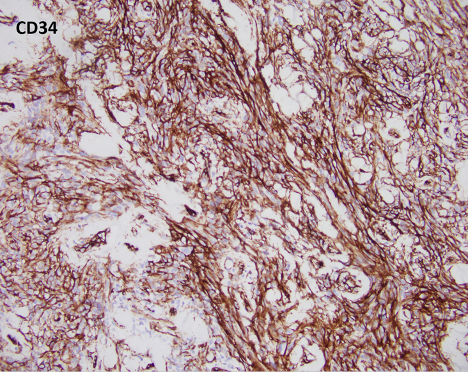

Myofibroblastoma (MFB) is an uncommon myofibroblastic lesion, typically seen in older patients. It occurs in both males and females and usually presents as a slow growing, palpable, painless breast mass. Most lesions are small, 1-4 cm; however, cases of giant myofibroblastomas have been reported. Histologically, the lesion is characterized by a well-circumscribed mass composed of spindle cells intermixed between bundles of hyalanized collagen. Because the neoplasm is myofibroblastic in origin, immunohistochemical markers such as Smooth Muscle Actin (SMA), Muscle Specific Actin (MSA), and Desmin are characteristically positive. Myofibroblastomas are also typically positive for CD34, estrogen receptor (ER), progesterone receptor (PR), and androgen receptor (AR). The cells of interest are negative for cytokeratins. Genetically, the entity is characterized by loss of 13q14 and 16q. As a result, there is inactivation of genes RB1 and FOXO1, and as such, loss of Rb expression via immunohistochemistry. Treatment typically consists of surgical excision with no additional therapy required.

All of the other answer choices may be considered in the differential diagnosis, especially on biopsy. Metaplastic carcinomas can be comprised of spindle cells with or without an epithelioid component. However, the stromal collagen is typically not present and the cytology is much more pleomorphic with frequent mitosis and an infiltrative growth pattern. Additionally, metaplastic carcinomas will be positive for cytokeratin immunohistochemistry and negative for hormone receptors ER/PR/AR, CD34, and desmin/myofibroblastic markers. Phyllodes tumors are also neoplasms of stromal differentiation. Phyllodes tumors, however, show both the presence of spindle cells and benign epithelium, typically creating a “leaf-like” architecture. IHC is positive for CD34 but Rb staining is retained. Pseudoangiomatous stromal hyperplasia (PASH) usually doesn’t form a mass; however, it is a myofibroblastic lesion with a similar staining pattern, SMA, desmin, ER, and PR positive. Histologically PASH has a dense collagenous stroma with prominent slit-like spaces. Additionally, the characteristic genetic alterations found in MFB are not present.